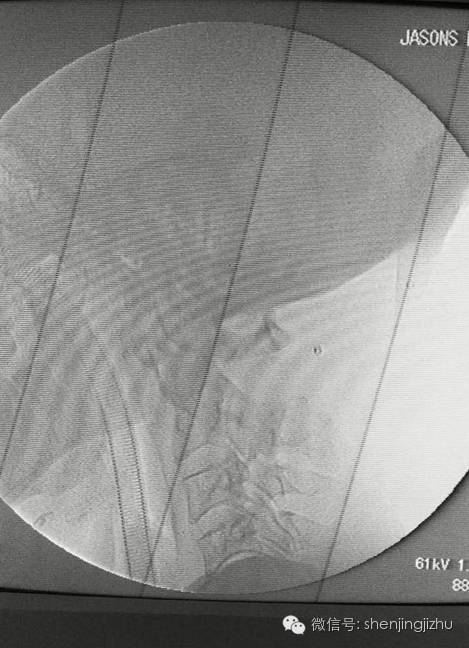

后路寰枢椎复位+枕颈融合术

术后影像: